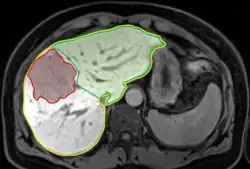

Zur Bestimmung der Restleberfunktion wird zunächst aus Schnittbildern mit einer geeigneten Software das Gesamtlebervolumen (VG) identifiziert. Anschließend wird der tumoröse Bereich (VT) markiert und die chirurgische Schnittfläche eingezeichnet, die die Aufteilung in Resektat- (VR) und Restlebervolumen (VFLRV, Future Liver Remnant Volume) ermöglicht (Abbildung 1). Das eben beschriebene, dezidierte Vorgehen ist nötig, da angenommen wird, dass das tumoröse Volumen keine CYP1A2-Aktivität innehat und somit keinen Beitrag zu der mittels LiMAx ermittelten Gesamtleberfunktion beiträgt. Zur Berechnung der FLRF wird folgende Formel genutzt: [4]